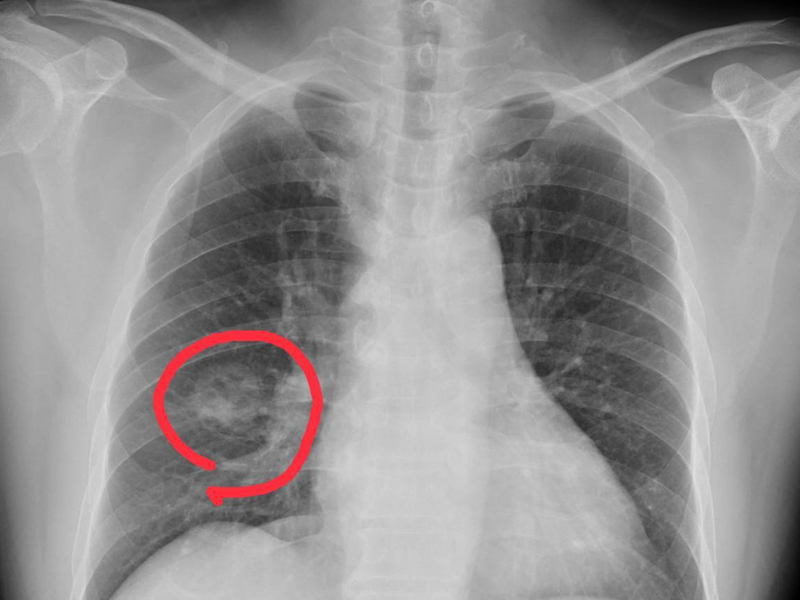

瀏覽:2086 吃飯快、吃飯慢的人,到底哪個更健康? | 瀏覽:1537 重大科學發現!革命性抗衰老方法 | 瀏覽:17183 手腳出現 4 種異常,可能是得肺癌了,千萬不要大意 |